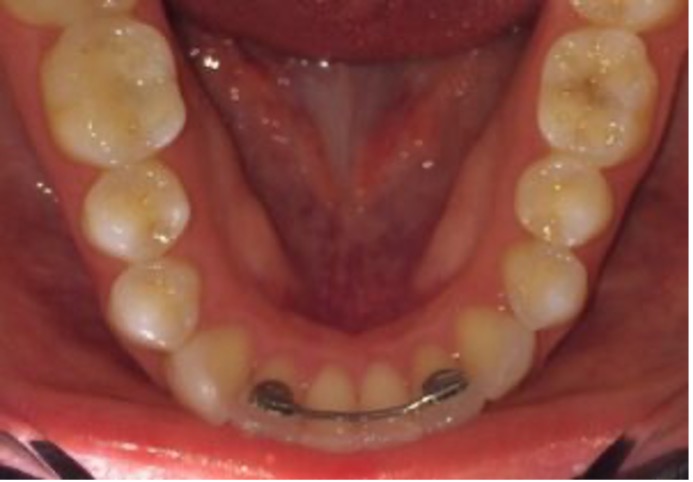

And who really cares about these tori bones? You should! When the tori bones form behind the lower teeth, they are effectively pushing the tongue backward and can compromise the airway to some extent. In some cases these tori bones are so huge that we need to have the oral surgeon remove them to make more room for the tongue. This is a bit of a rough surgery as the surgeon has to chisel these bones away. As you can see in the photo below, the large tori bones behind the lower teeth are pushing this person’s tongue back into the throat. This can be contributory to sleep apnea and many health issues due to sleep disordered breathing. By cutting away the tori bones, the tongue can then move around much better.